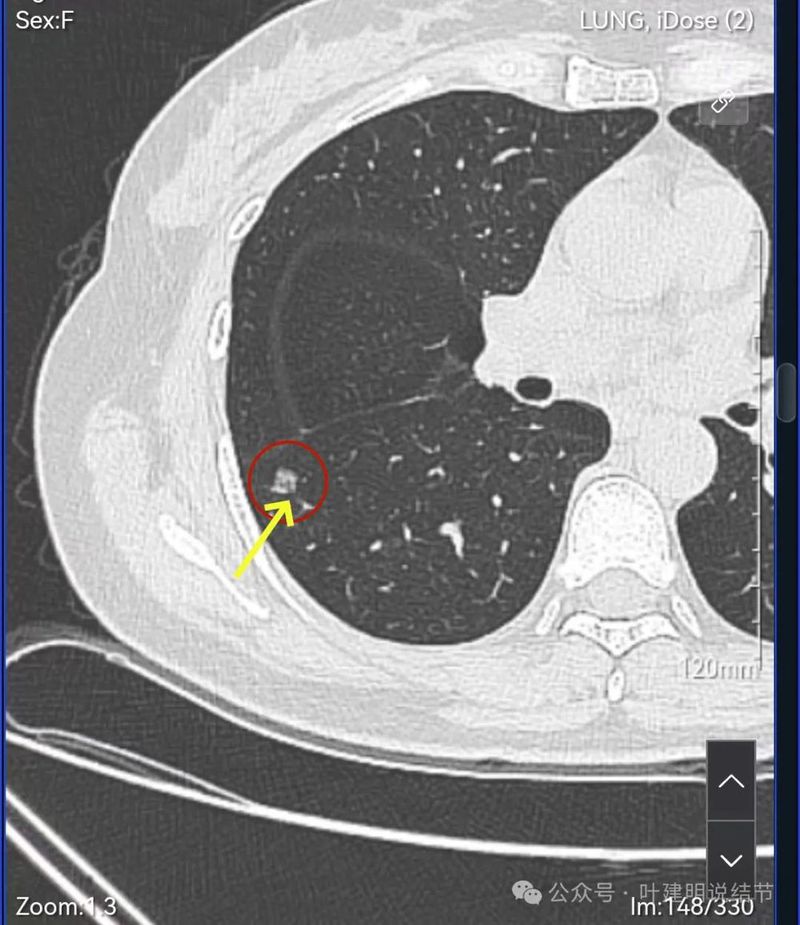

灶内血管穿行,表面分叶、中间空泡,实性成分。